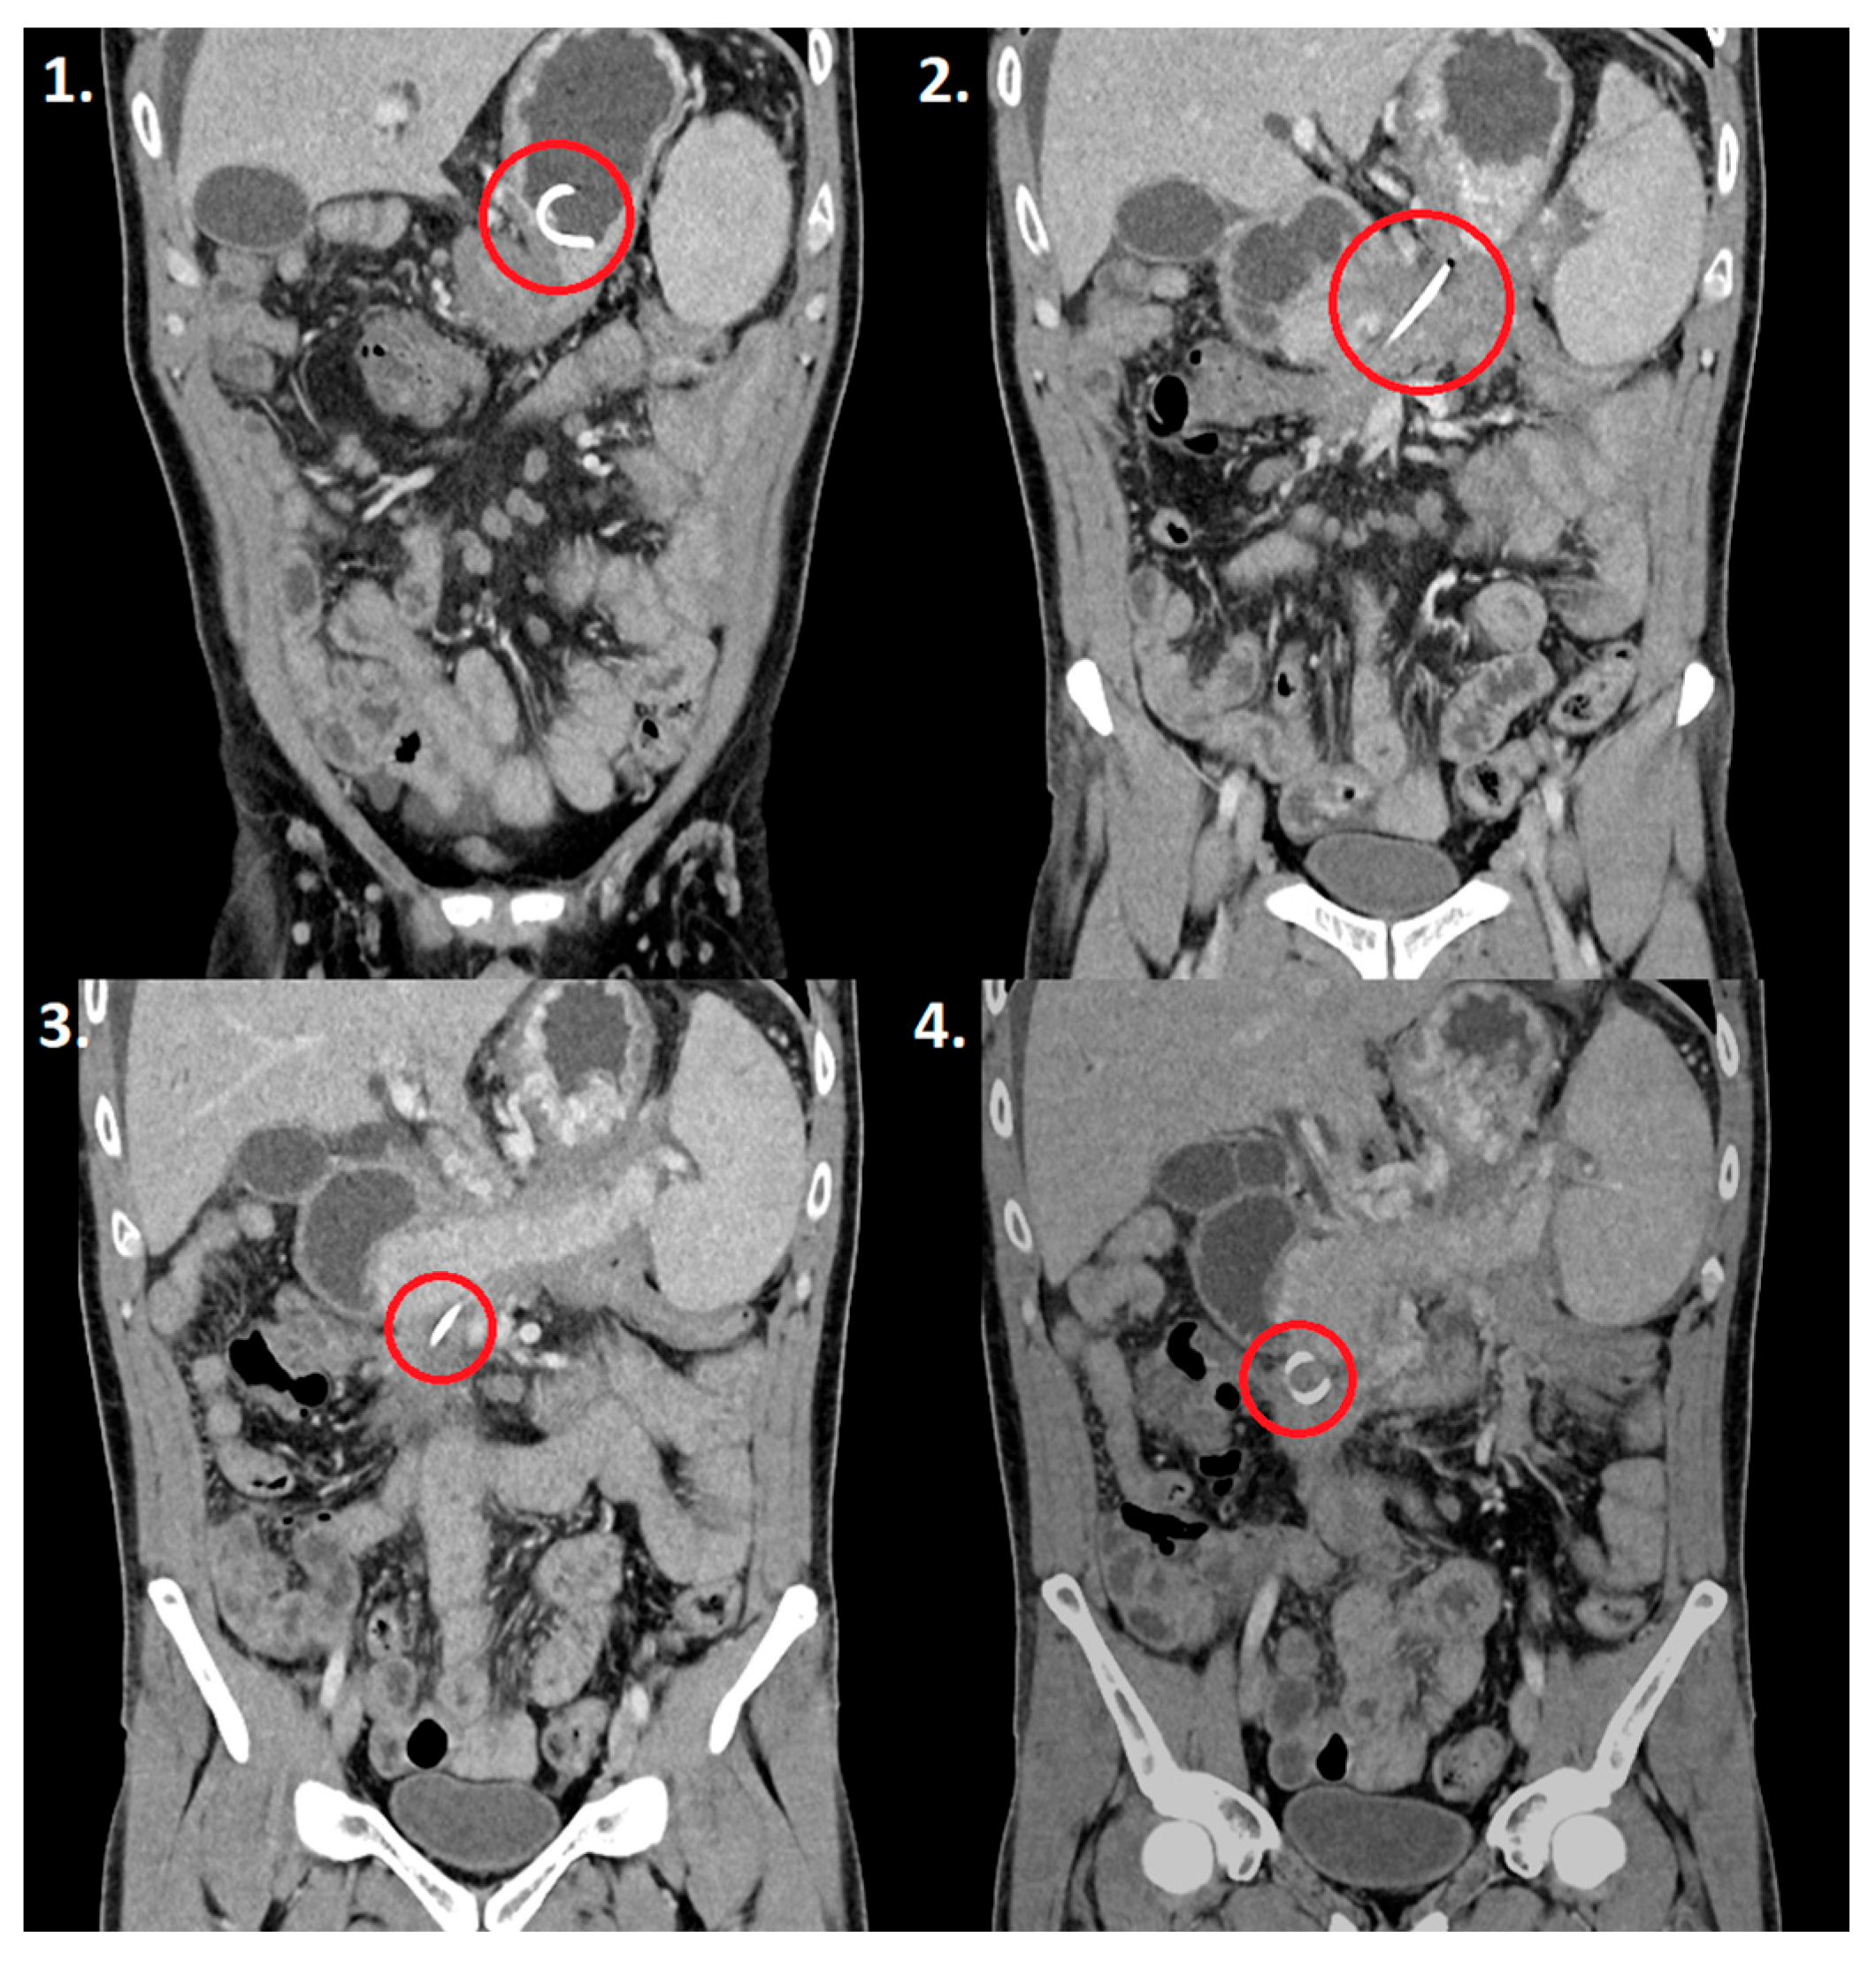

2. Detailed Case Description

2.2. Results